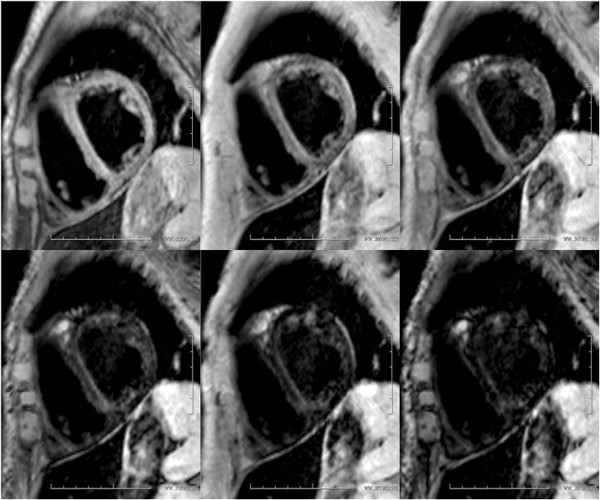

Det ble utført CT-undersøkelse av leveren, som viste patologisk forhøyet signal med gjennomsnittlig tetthet 100 HU (Hounsfield Units) (fig 2, fig 3), klart forenlig med jernavleiring i lever. På bakgrunn av dette ble sannsynligheten for toksisk oppladning i leveren vurdert som så stor at risikoen ved en leverbiopsi ikke var rettferdiggjort. Det ble også gjort MR cor ved universitetssykehuset, der T2-vektet bilde viste maksimalt patologiske verdier på < 10 ms (> 20 ms), forenlig med jernavleiring i myokard (fig 4). Vi fant ingen validert måte å måle jernavleiring i pancreas og thyreoidea på.